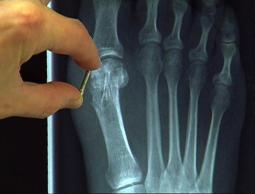

ابتكر فريق من الباحثين في كلية علوم الكيمياء بجامعة التقنية العليا في مدينة برنو التشيكية سائلا يشبه المراهم قالوا إنه سيكون البديل عن الجبس والبراغي الفولاذية التي تعالج جميع أنواع كسور العظام في الجسم وأنه يعمل بطريقة أسرع في الشفاء.

وكشف رئيس قسم العيادة العظمية لدائرة براغ الرابعة ميريك بروخاسكا أن هذا الابتكار الجديد تم اكتشافه من طرف مختصين تشيكيين بالكيمياء، مشيرا إلى أنهم أطلقوا على المرهم الجديد اسم (لاصق العظام) وأنه سيكون له الفضل في تغيير طريقة العلاج التقليدية المتبعة حتى الآن وهي تركيب الجبس والبراغي في مكان الإصابة.

وأضاف بروخاسكا أن طريقة وضع هذا المرهم أو السائل الذي يتحول إلى مادة تقوم بتثبيت العظام وإعادتها إلى وضعها الطبيعي تتم عبر إبرة حقن يستعين بها الطبيب بمساعدة جهاز كمبيوتر يشير وبدقة إلى مكان الكسر لتقوم هذه المادة بتثبيت مكان الإصابة محدثة التفافا حول العظم ومكان الفراغ نتيجة الإصابة.